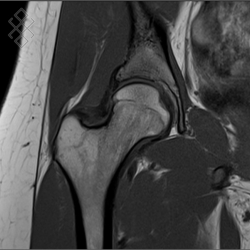

IRM de la Hanche